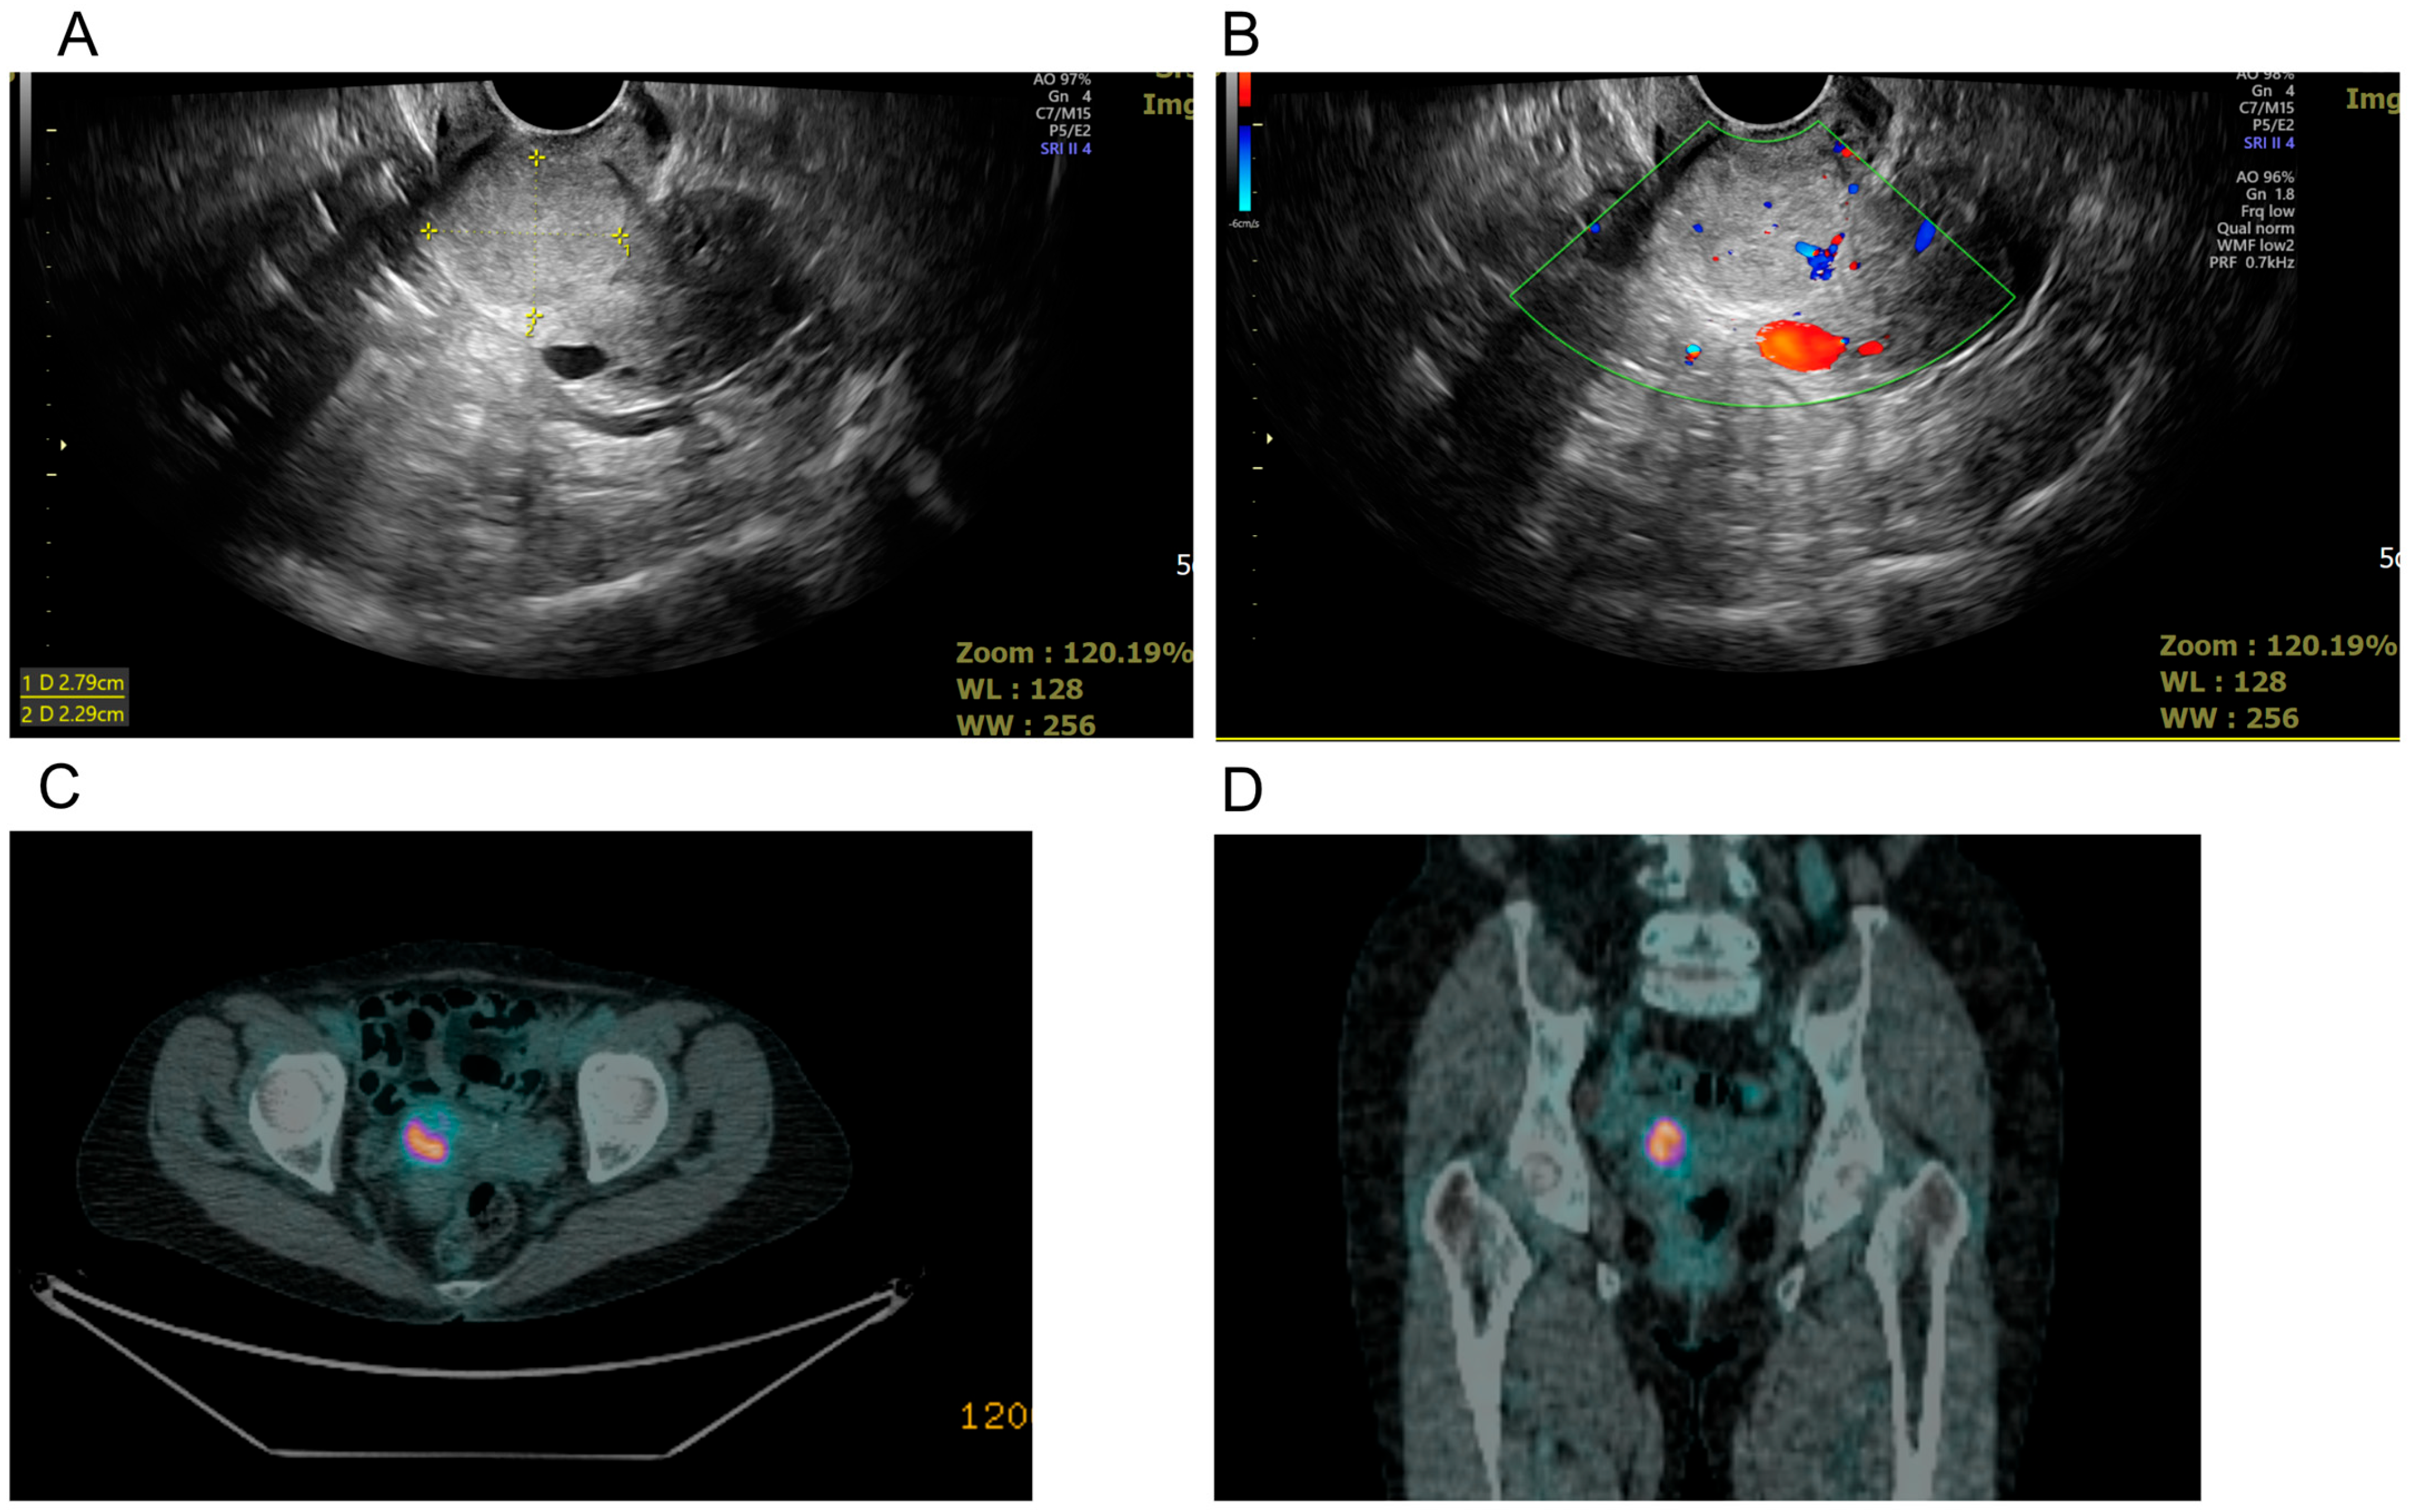

A 72-year-old Asian female without underlying diseases presented with postmenopausal vaginal spotting for 1 month. Initial evaluation at a local hospital detected a 3 cm cervical tumor, leading to referral for further investigation. Endocervical curettage confirmed LCNEC of the cervix. She reported no other symptoms, and her medical history was unremarkable except for menopause at 53 years and three vaginal deliveries. Physical examination revealed vaginal staining with a small tumor dropped from the endocervix, and laboratory tests showed normal blood counts, liver, and kidney function, with tumor markers (CA 125, CA19-9, CEA, and SCC) within normal limits. Imaging studies, including vaginal ultrasound (Figure 1A,B) and positron emission tomography–computed tomography (PET-CT) (Figure 1C,D), identified a hypermetabolic 2.7 cm cervical tumor confined to the uterus. A cervical biopsy was performed, and LCNEC of the cervix was diagnosed.

Figure 1.

Multimodal imaging of pelvic lesion. (A) Transvaginal grayscale ultrasound image showing a well-defined solid mass measuring approximately 2.79 × 2.29 cm in the pelvic region (+..+1: dimension 1). (B) Transvaginal color Doppler ultrasound demonstrated increased vascularization within the lesion, suggesting neovascularity. (C) Axial PET/CT fusion image highlights hypermetabolic activity within the lesion, indicating potential malignancy. (D) Coronal PET/CT fusion image further localizes the hypermetabolic pelvic mass about surrounding anatomical structures.